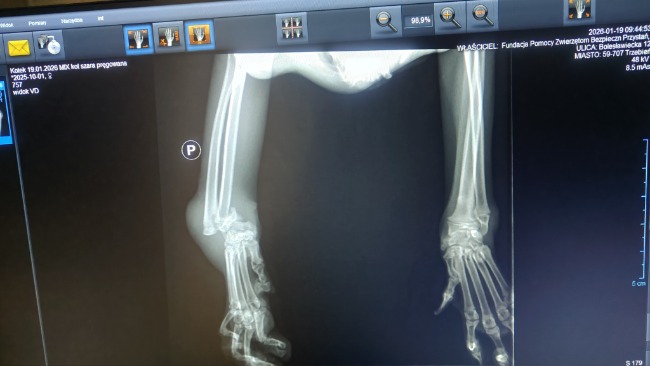

RTG w lecznicy odebrało nam dech.

Ale dramat, który rozgrywa się w ciele tego maleństwa, widać aż za dobrze na jednym obrazie.

Zwichnięcie nadgarstka.

Kości przemieszczone.

Wykręcone wokół własnej osi.